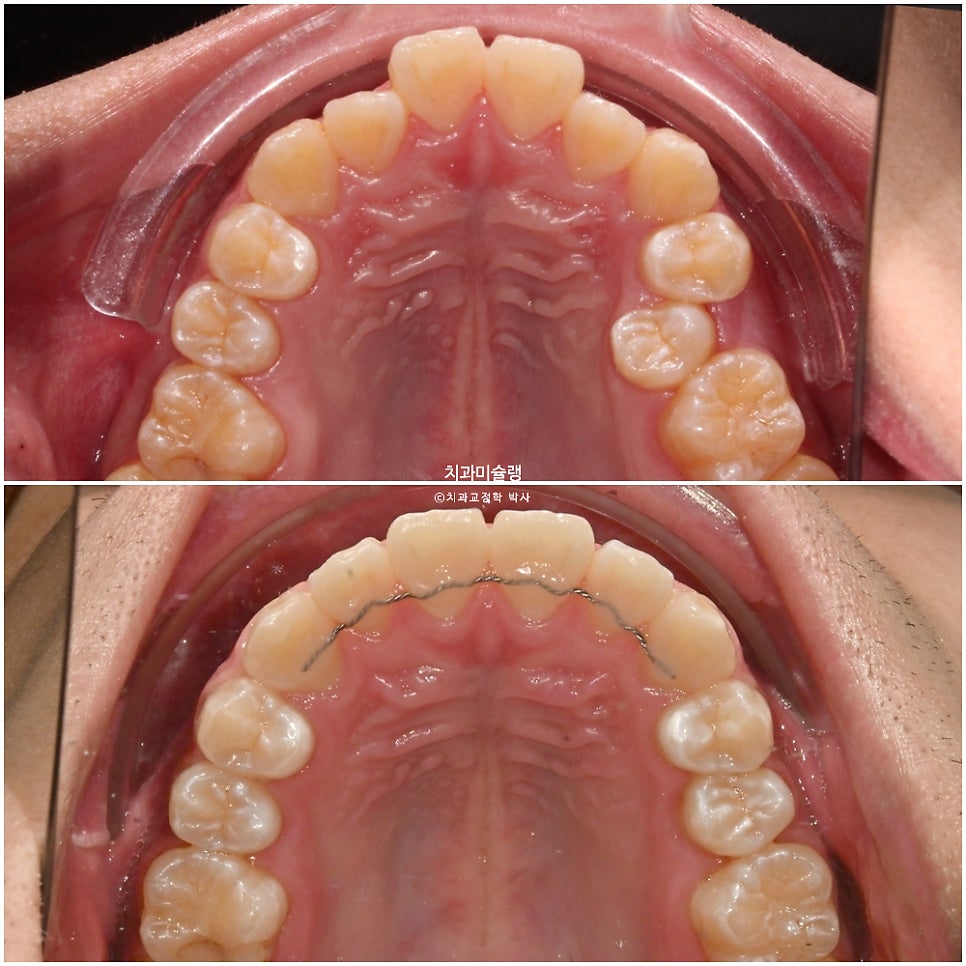

2024년 1월, 교정치료를 위해 내원한 20대 초반 환자분 입니다.

{IMG_2}

앞니에 약간의 개방교합이 보이고

앞니가 거꾸로 물리는 반대교합입니다.

치아만 거꾸로 물리는에 아닌, 골격성 3급 부정교합으로 양악수술이 필요한 주걱턱 입니다.

어금니도 마찬가지로 3급 교합관계를 보입니다.